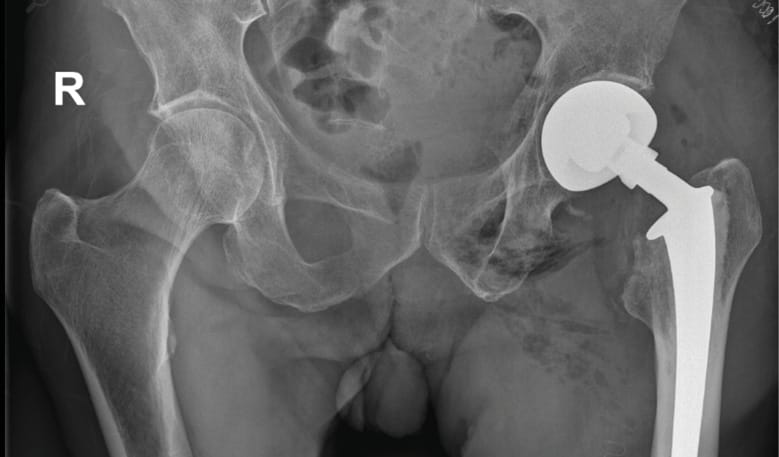

Case 2: Femoral neck fracture in elderly patient with poor soft tissue tension and large offset (91-year-old female)

Traumatic fragility fracture of the left femoral neck. Due to a large offset, the original anatomy could not be restored by hemiarthroplasty using a lateralized stem alone. After several intra-operative trials, soft tissue tension could adequately be balanced with the application of a BioBall® 4XL adapter. A stable articulation without any further instability could be accomplished.